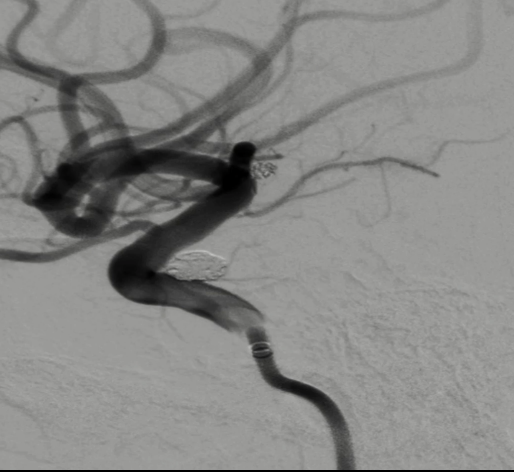

术前外院 DSA 2025-02

箭头所指右侧A1微小动脉瘤

工作位正位造影(图片)

工作位侧位造影(图片)

术后正侧位造影:Raymond Ⅲ级

术后支架重建:支架打开良好,近端Marker位于颈内动脉分叉处